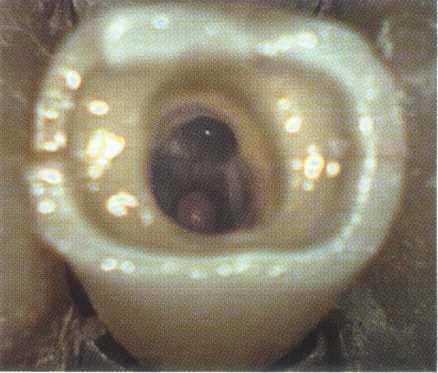

Maxillary Molars

Treatment of maxillary molars is never routine (Figure 2-22). In a recent study of maxillary first and second molars an MB2 canal was found in 96% of the mesiobuccal roots of maxillary first molars and 94% of the maxillary second molars. Approximately 54% were located in the traditional access opening, 31% were found with the use of a bur, and 10% were found with the aid of a microscope. The MBZ canal orifice was found on average 1.82 mm lingual to the main MB canal orifice.9 In another study of the maxillary first molar using microscopy, the MB Z canal was located in

93% of first molars and 60% of second molars4 (Figures 2-23 and 2-24). The difficulty in access, high percentage of fourth and even fifth canals, and root curvatures put even the "routine" maxillary molar in a high-risk category.3 Complicating factors such as limited opening, crowns, changes in tooth angulation, tooth position, and calcification make predictable treatment of these teeth challenging for even the most experienced clinician trained in microscopy, ultrasonics, and rotary instrumentation.

Guidelines for canal location in the maxillary first molar (Figure 2-25) differ from that in the maxillary second molar. In the maxillary first molar the MB canal is located under the mesial buccal cusp (see Figure 2-25, D). The MBZ canal is located mesial to a line from the

MB canal toward the palatal canal (see Figures 2-25, E, and 2-26). The DB canal is located distal to the MB canal in the buccal groove area, slightly lingual to the MB canal (see Figure 2-25, G). The palatal canal is generally the largest canal and is located under the mesiolingual (ML) cusp (see Figure 2-25, F). These general locations remain the same as the pulp calcifies with age (Figure 2-27). Although these general principles apply to the maxillary second molar, the chamber may be narrower, resembling a straight line (see Fig. 2-55).